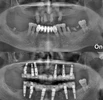

Fotoğraflar